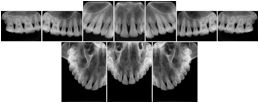

Intra-oral radiography typically involves acquisition of multiple images of various parts of the dentition. Many digital radiographic systems offer customized templates that are used for displaying the images in a study on the screen. These templates may also be referred to as mounts or view sets. The Structured Display Object represents a standard method of encoding and exchanging the layout and intended display of Structured Displays. A structured display object created in this manner could be stored with a study and exchanged with images to allow for complete reproduction of the original exam.

1. A patient visits a General Dentist where a Full Mouth Series Exam with 18 images is acquired. The dentist observes severe bone loss and refers the patient to a Periodontist. The 18 images from the Full Mouth Series along with a Structured Display are copied to a DICOM Interchange CD and sent with the patient to see the specialist. The Periodontist uses the CD to open the exam in his Dental Radiographic Software and consults via phone with the General Dentist. Both are able to observe the same exam showing the images on each user's display using the exact same layout.

Intra-oral Full Mouth Series Structured Display

Figure OO-1. Intra-oral Full Mouth Series Structured Display